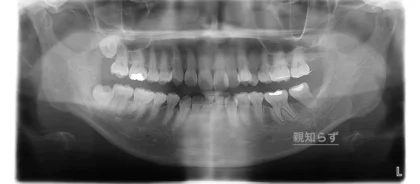

当院にご紹介でいらっしゃった患者さんで、左下の歯の痛みで他院で治療を受けていた患者さんです。当院でレントゲンを撮ると、親知らずの手前の歯の神経の治療を受けていました。レントゲン写真をみると大きく穴が空いており、なおかつ親知らずの影響もあり歯周病にもなっていた為、かなり状況が悪い事をお伝えして、治療方法をいくつか提示したところ、親知らずを矯正で状態の悪い歯の位置に移動させる事になりました。CTも撮影してご説明しました。

CTはレントゲンでは判りにくい部分を視覚的に患者さんに説明できるので、患者さんがイメージしやすく、当院ではインプラントや根の治療で活用しています。